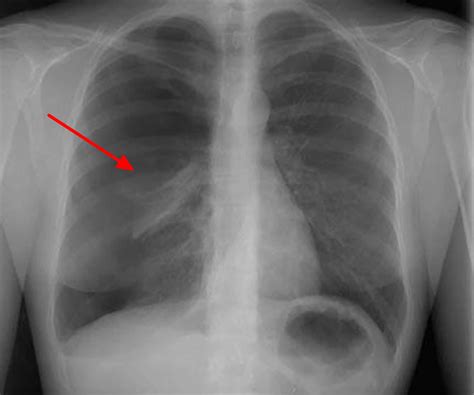

• Imaging studies: Chest X-rays are the most common imaging study used to diagnose pneumothorax ex vacuo. In some cases, a CT scan may be ordered to provide more detailed images of the lungs and pleural space.